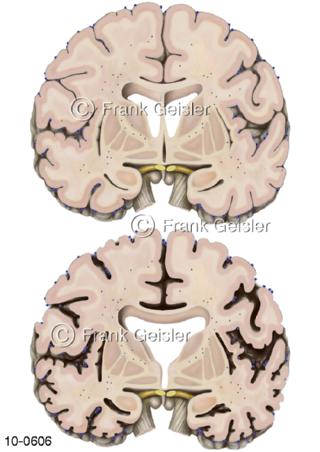

Bildergalerie Nervensystem

Bilder zum Nervensystem,dem Gehirn, Teil des zentralen Nervensystem, Zentralnervensystem ZNSmit Rückenmark, Abbildungen zum Nervengeflecht (Nervenplexus), die Verflechtungen von Nervenfasern, aus der Wirbelsäule hervortretende Nervenäst sowie Nervenzellen der Nerven